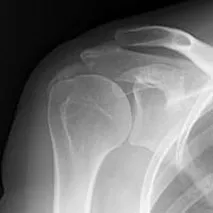

診断は実際の症状やレントゲン、超音波、MRIといった画像診断を用いて総合的に行います。